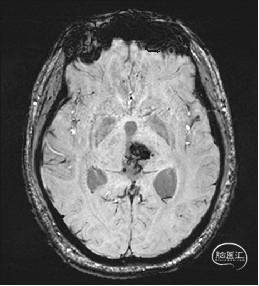

术前MRI检查

术前MRI检查提示左侧丘脑中脑海绵状血管瘤并卒中,梗阻性脑积水;

诊断:1.左侧丘脑中脑海绵状血管瘤并卒中,2.梗阻性脑积水;

年轻患者,较短时间内发生左侧丘脑二次出血,出现右侧面部及上肢麻木,复视,第二次出血后并发梗阻性脑积水,出现头痛。结合病史、神经系统体征、头颅CT及MRI检查,诊断左侧丘脑及中脑CM并卒中、脑积水明确,并导致了神经功能障碍,具备手术指征。

本例患者磁共振检查清晰显示病变位于左侧丘脑中脑区域,且位于丘脑内下方向中脑顶盖延续,病变的上部、前部、外侧部都有重要的神经组织,因此,手术从上方、前方、外侧方向切除病变均难以实施;